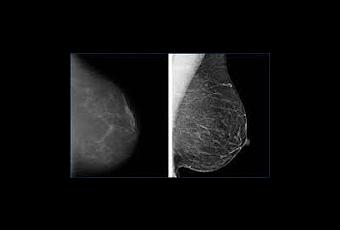

Una Investigación realizada en Seattle (Estados Unidos), publicada

en Archives of Internal Medicine', encontró que las mamografías podrían no reducir la mortalidad por

cáncer de mama y a su vez, provocar un sobrediagnóstico,. Para llegar a esta

conclusión, los expertos analizaron mamografias

de casi 16 millones de mujeres mayores de 40 años de 547 condados de

Estados Unidos. De ellas solo 53 000 fueron diagnosticadas con Cáncer de Mama y

a pesar que el numero de mamografías aumento la mortalidad permaneció igual ya

que la mayoría de los cánceres adicionales detectados en

el cribado eran tumores pequeños. De hecho, no hubo un aumento en el diagnóstico de los grandes tumores.

Por tanto, los resultados han sugerido que las mamografías pueden llevar a un

sobrediagnóstico porque capturan principalmente los tumores más pequeños. Por tanto siempre es recomendable la palpacion de las mamas al finalizar el periodo mestrual y complementar con una ecografia mamaria.